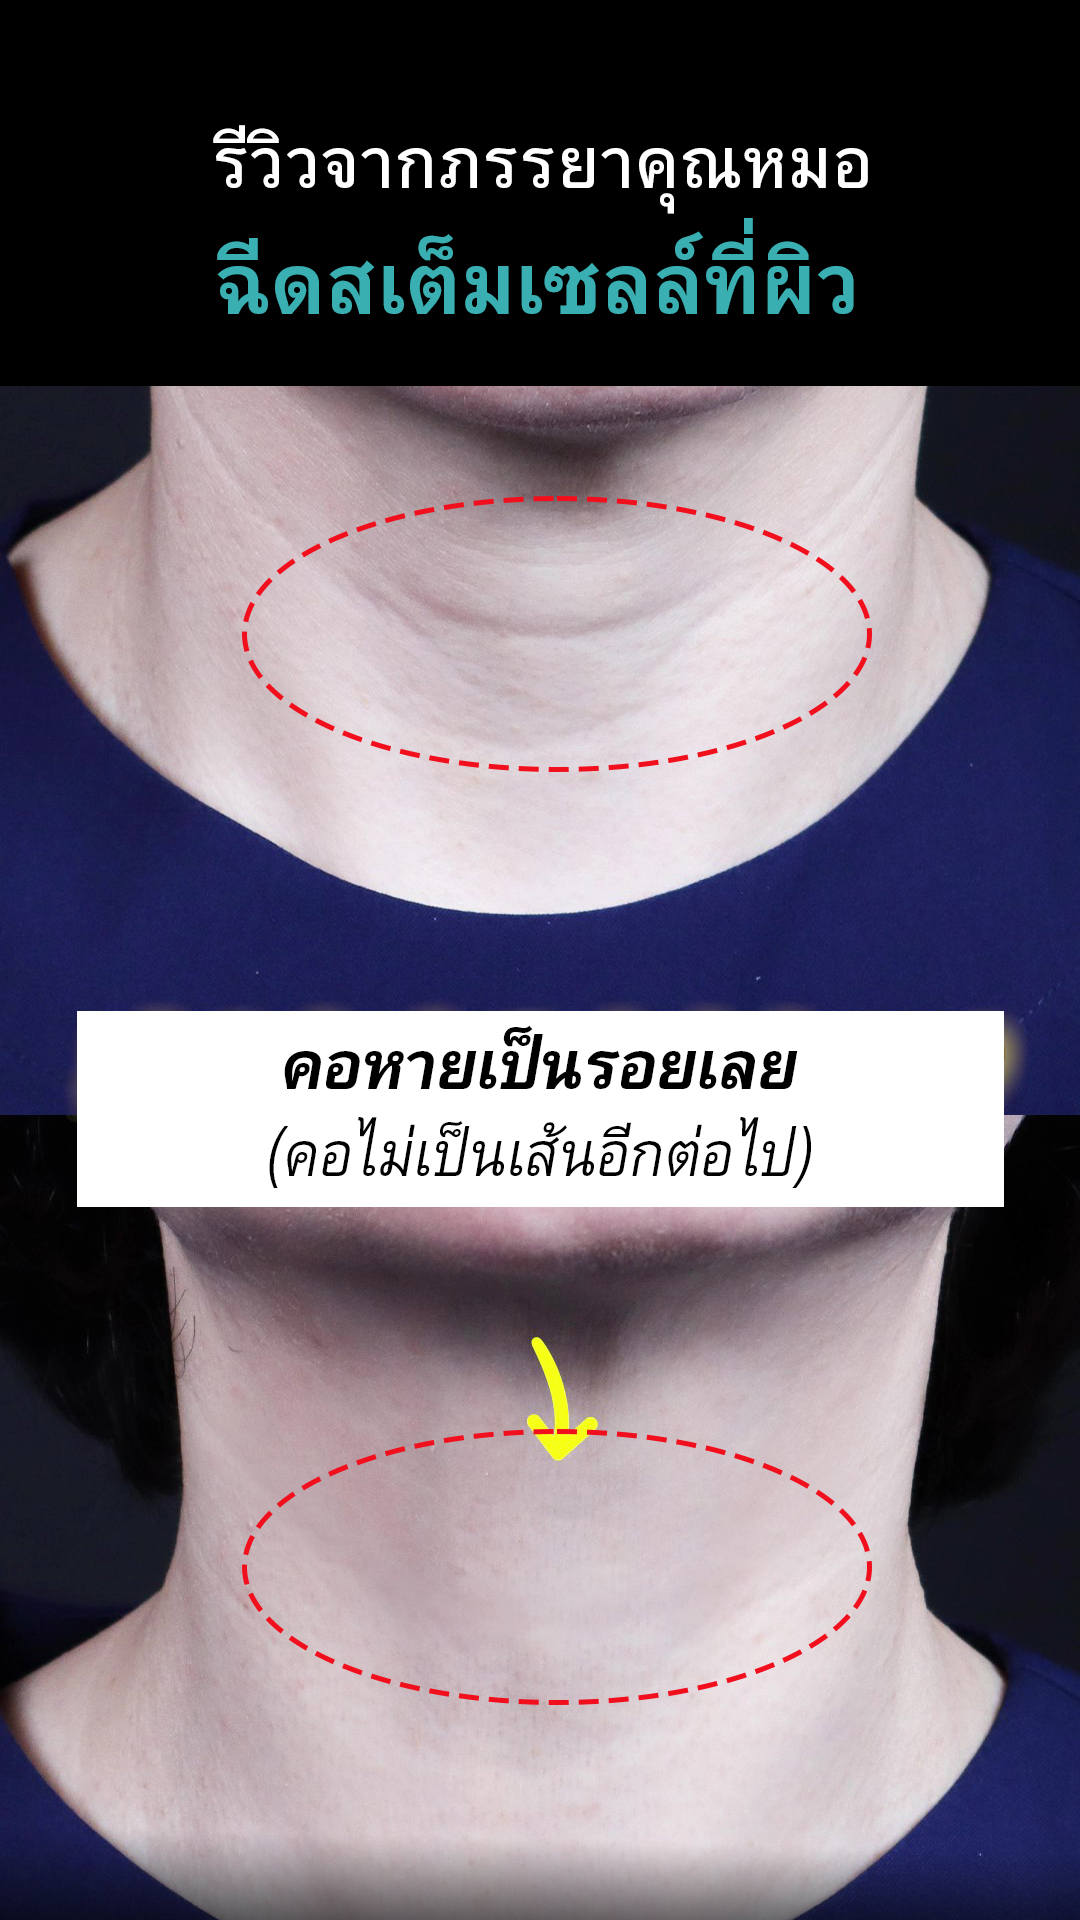

คอลลาเจน เป็นเส้นใยโปรตีนที่เป็นส่วนประกอบของผิวหนัง ช่วยยึดเกาะ

เพิ่มความยืดหยุ่นและความชุ่มชื้นแก่ผิว โดยปกติร่างกายจะสามารถผลิตคอลลาเจนได้เอง

แต่เมื่ออายุมากขึ้น ร่างกายจะสามารถสร้างคอลลาเจนได้น้อยลง

ซึ่งทำให้ผิวหนังหย่อนคล้อยและเกิดริ้วรอยตามวัยได้

คอลลาเจน เป็นเส้นใยโปรตีนที่เป็นส่วนประกอบของผิวหนัง ช่วยยึดเกาะ

เพิ่มความยืดหยุ่นและความชุ่มชื้นแก่ผิว โดยปกติร่างกายจะสามารถผลิตคอลลาเจนได้เอง

แต่เมื่ออายุมากขึ้น ร่างกายจะสามารถสร้างคอลลาเจนได้น้อยลง

ซึ่งทำให้ผิวหนังหย่อนคล้อยและเกิดริ้วรอยตามวัยได้